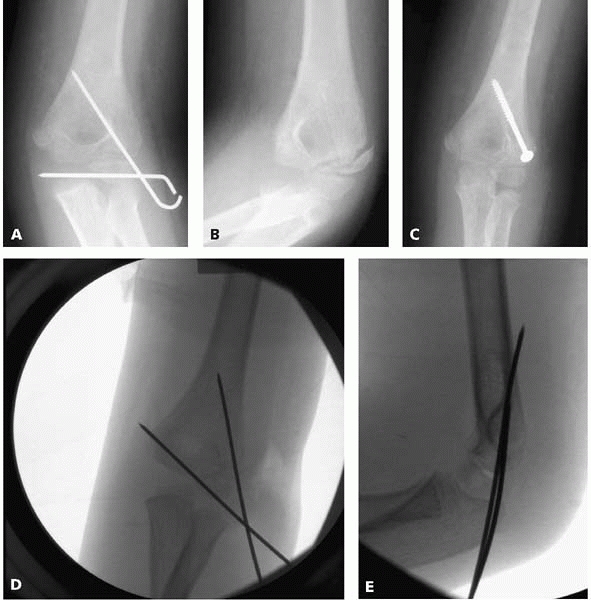

▪ FIGURE 6-1 A: AP view of a lateral condyle fracture demonstrating less than 2 mm displacement. B: Lateral view of a lateral condyle fracture demonstrating less than 2 mm of displacement. C:

Oblique view, looking at the lateral side of the elbow tangentially, showing greater than 2 mm of displacement. Without this radiograph, one may have assumed there was less than 2 mm of displacement, and treated the fracture nonoperatively. |

use in determining treatment or predicting outcome. If the amount of

maximum fracture displacement in all radiographs is ≤2 mm, then

nonoperative treatment with immobilization is indicated. Remember that

the AP and lateral views may underestimate the extent of fracture

displacement, so an oblique view is necessary (Fig. 6-1) when considering

nonoperative treatment. A prospective investigation of 112 lateral